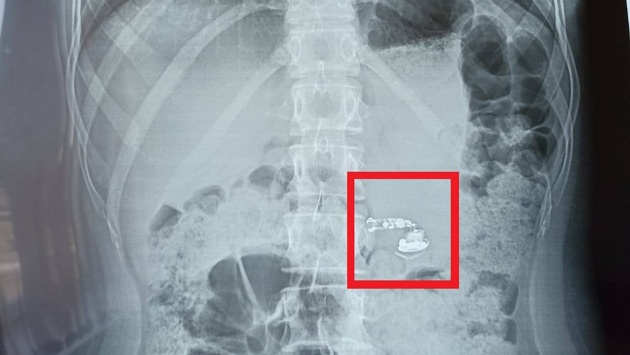

В больнице девочке сделали рентген брюшной полости и фиброгастроскопию, обследовали пищевод, желудок и 12-перстную кишку. В итоге наушник нашелся в кишечнике. Подростка положили в отделение детской хирургии, но, к счастью, операция не понадобилась. Наушник вышел из организма естественным путем.